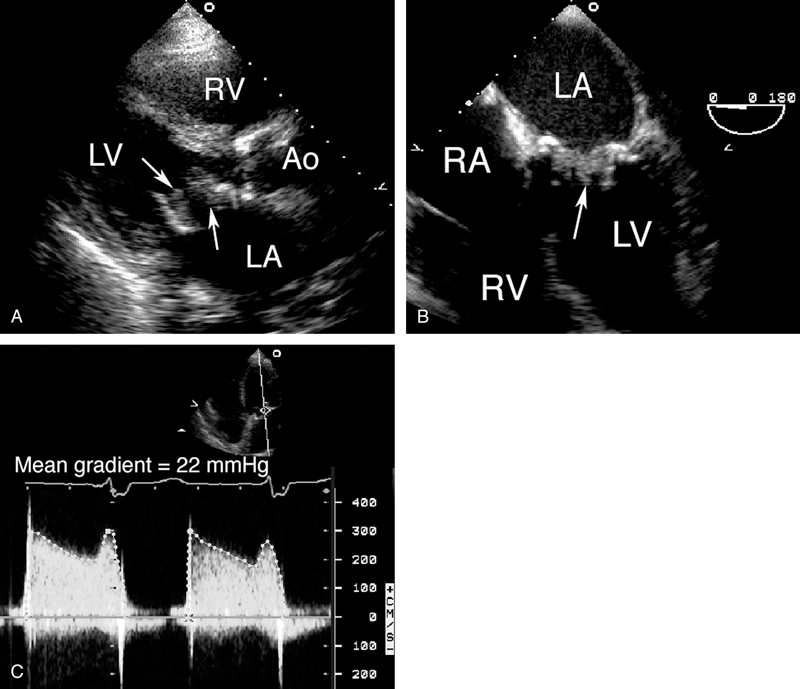

فحوصات تشخيصية لبعض امراض القلب والشرايين التاجية